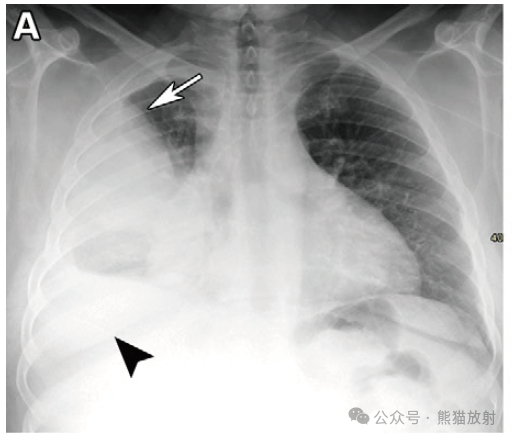

平片和CT在间皮瘤患者治疗中的作用。(A,B) 44岁男性,胸膜间皮瘤。胸部X线片 (A) 显示右半胸有大片阴影(箭头)和中等量右侧胸腔积液(箭)。冠状胸部CT平扫(B) 显示右半胸见较大的软组织密度肿块(箭)和相关的胸膜不规则增厚(箭)。右侧胸腔积液(箭头)。(C) 46岁男性,胸膜间皮瘤。胸部轴位CT平扫显示左侧胸膜软组织密度肿块和相关的胸膜钙化斑(箭)。